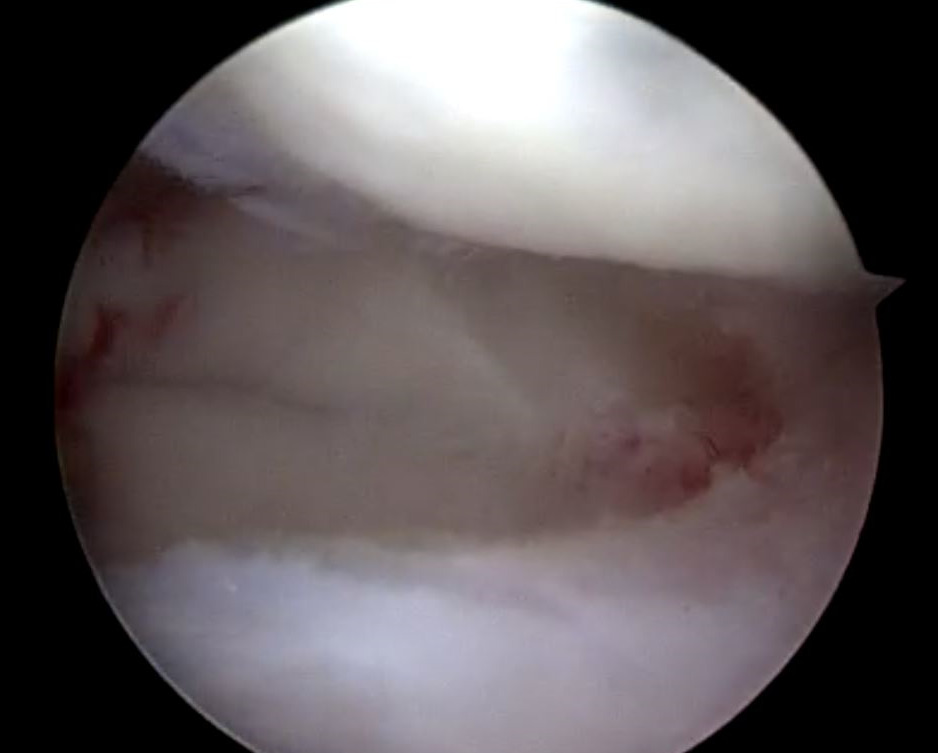

The tear pattern involved the periphery of the lateral meniscus, extending along the meniscocapsular junction from zones I though III (Figure 6).

The anterior and posterior roots of the lateral meniscus were intact (Figure 7).